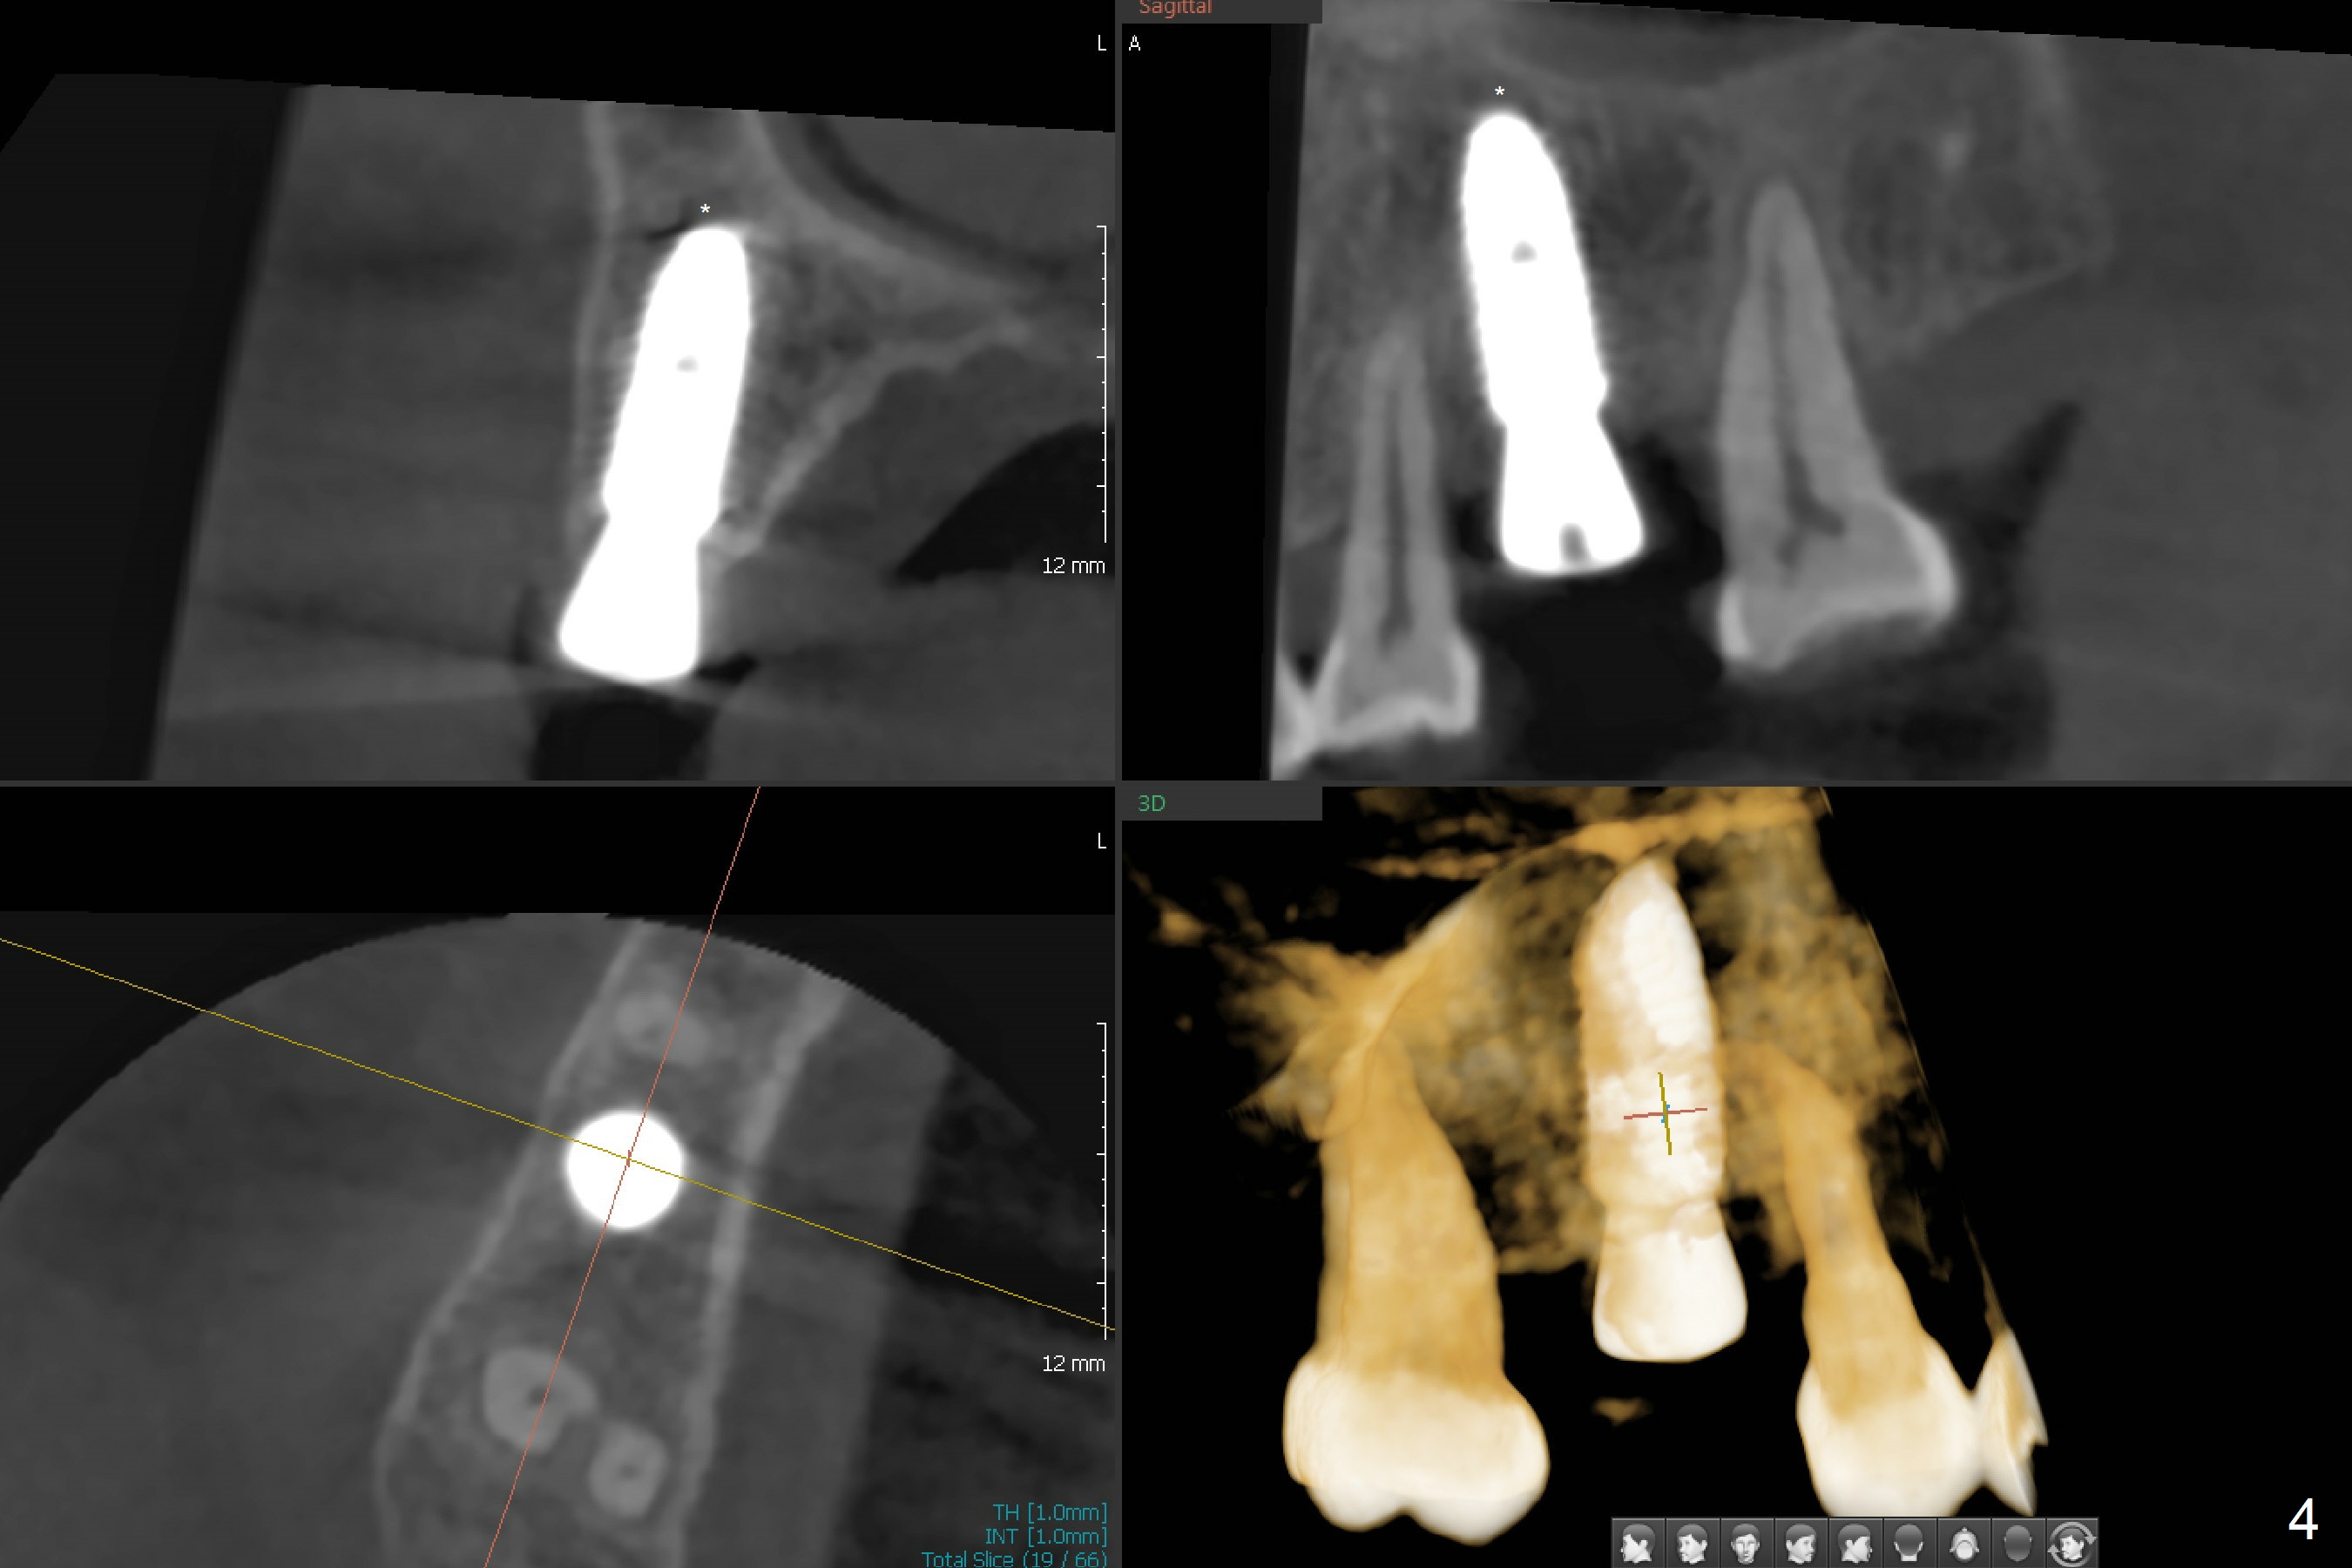

In order to place a 5x11.5 mm implant at #3 completely in depth, the preop CBCT coronal section is reanalyzed (Fig.1). It appears that extra 1 mm osteotomy does not perforate the sinus floor. After finishing osteotomy according to the guide plan, a 3.5x13 mm drill is used ~ .5 mm shy of the depth without sign of sinus membrane leakage. The implant is placed with apparently satisfactory depth, but it is quite close to the curved root tip of the neighboring tooth (Fig.2,3). In fact postop CBCT shows that there is a clearance (Fig.4). To prevent the similar event in the future, the implant should be designed slightly distal. The postop CBCT also shows that the extra depth is not necessary (Fig.4 *); it seems that the inherent 1.2 mm drill tip is sufficient for the depth overprep. The implant is stable for impression 6.5 months postop (Fig.5), whereas that placed immediately free hand is unstable 7.5 months postop. Two weeks later, the patient experiences severe pain when the abutment is being retightened. The crown at #3 is delivered 3 months later (9 months postop). It appears that the bone heals slow in this patient.